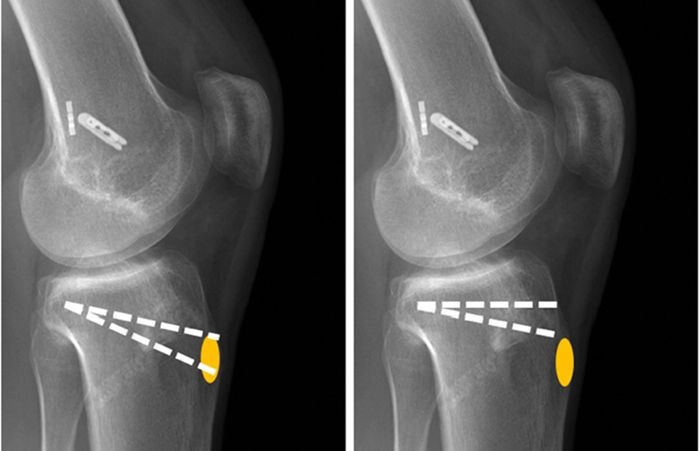

Osteotomi ameliyatı

DOME Shaped

Bu yöntemde, osteotomi eklem etrafında küre ve çanak şeklinde yapılır, osteotomi bölgesinin alt kısmı dikey eksen etrafında döndürülür - osteotomi sonrası küresel ve yarım daire şeklindeki kemik kırılır ve organ eksenindeki sapma ve deformite düzeltildikten sonra sabitlenir. Bu yöntemde uzuvlarda kısalma ve uzama olmaz ve teknik olarak daha zordur.